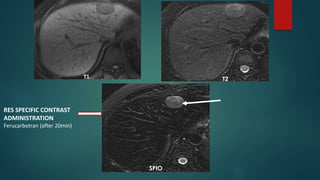

T1 T2

SPIO

RES SPECIFIC CONTRAST

ADMINISTRATION

Ferucarbotran (after 20min)